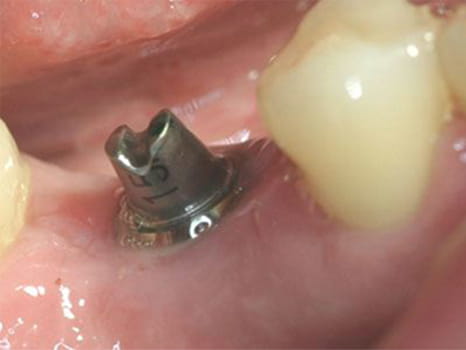

Implantat nach 3-monatiger Einheilphase

Implantat-vorher

Situation im Mund vor...